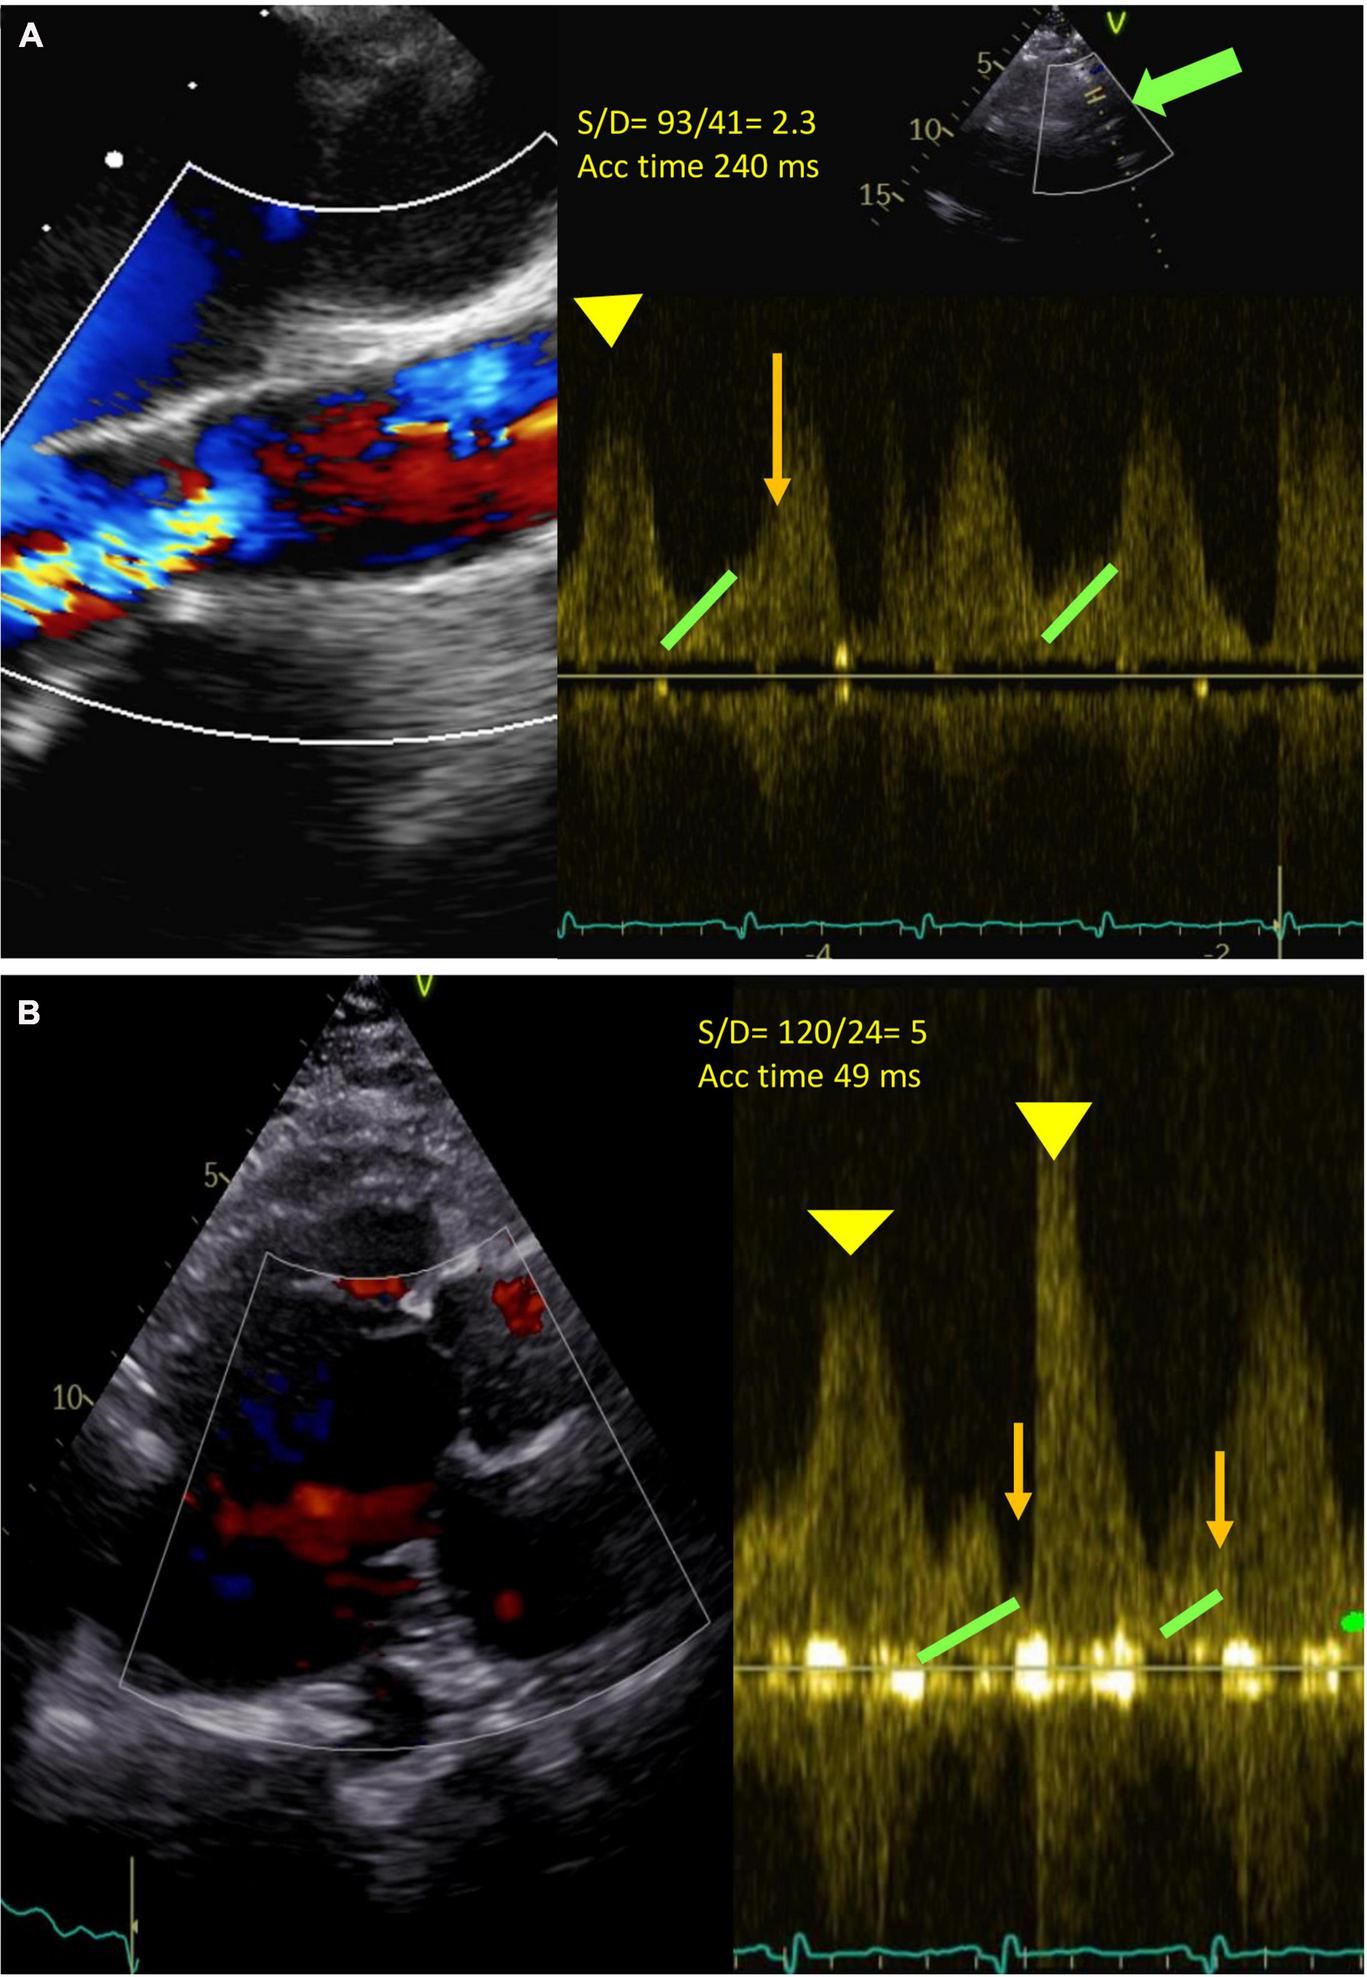

AR assessment under LVAD

Traditional TTE tends to underestimate the severity of AR as it occurs throughout the cardiac cycle due to insufficient residual LV contractile forces to oppose the backflow in systole, thus even a relatively small AV orifice can account for severe AR. Aortic flow, as a result, becomes highly dependent on global hemodynamics such as LV pre-load, residual contractility, and heart rate (77). Furthermore, the quantitative parameters (pressure half time, vena contracta, proximal iso-velocity surface area) are unreliable in this context since the determinant factor to the assessment of regurgitant severity in a CF-LVAD patient is the measure of flow over time. In addition to the traditional parameters, other specific measurements are suggested to improve AR severity stratification such as those reported in Table 5. For example, pulsed wave (PW) Doppler of the outflow cannula is important for documenting laminar, unidirectional, low-peak velocity flows, and no regurgitation. The PW sample volume is placed at least 1 cm from the anastomosis (Table 5) and a pulsatile flow pattern is characterized by phasic changes in flow throughout the cardiac cycle, reaching the maximum during systole and minimum during diastole. This signal can be used to calculate two parameters: (1) peak systolic-to-diastolic (S/D) velocity ratio, which correlates negatively with AR, and (2) diastolic acceleration time, which correlates positively with AR (Figure 3) (81, 82). Diastolic acceleration time is the diastolic slope from the onset to the end of diastole and the S/D ratio is calculated by dividing the peak systolic velocity by the end diastolic peak velocity. An S/D ratio less than 5.0 and/or a diastolic acceleration time greater than 49.0 cm/s corresponds to at least moderate AR, defined as a regurgitant fraction > 30%. The relationship between diastolic flow on the outflow cannula and AR is self-evident: as AR worsens, diastolic flow through the outflow cannula increases (81). However, in our experience, it is not always easy to be accurate since the outflow cannula might not be seen and/or the PW sample is not aligned with the flow of the cannula.

FIGURE 3

(A) Severe continuous (holo-systolic and holo-diastolic) aortic regurgitation (AR). Green arrow: outflow cannula. Pulse Doppler (PW) at about 1 cm from the outflow cannula (bold green arrow). Diastolic acceleration time 49 ms (orange line), S/D ratio 93/41 = 2.3 (<5 significant AR) (Yellow head arrow: systolic wave; green head arrow: end Diastolic velocity). Acceleration time 240 ms. (B) No AR. S/D 53/10 = 5. Acceleration time 49.